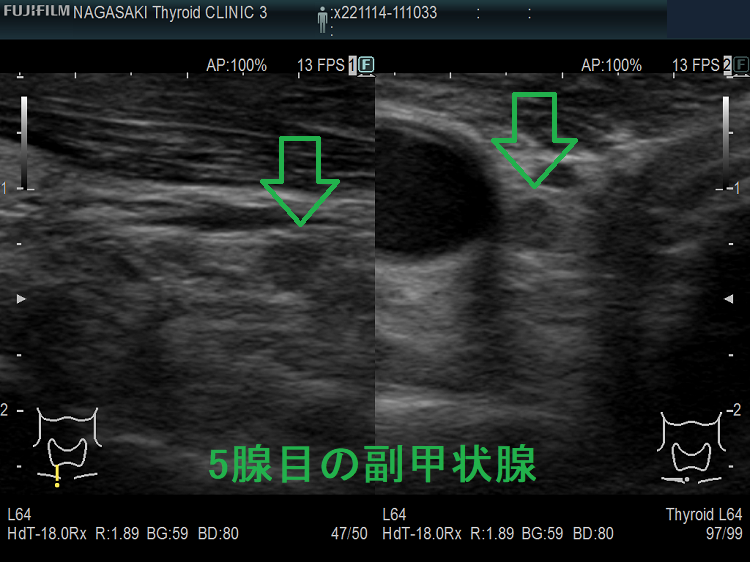

高カルシウム血症の程度と副甲状腺腫の大きさは必ずしも比例しない